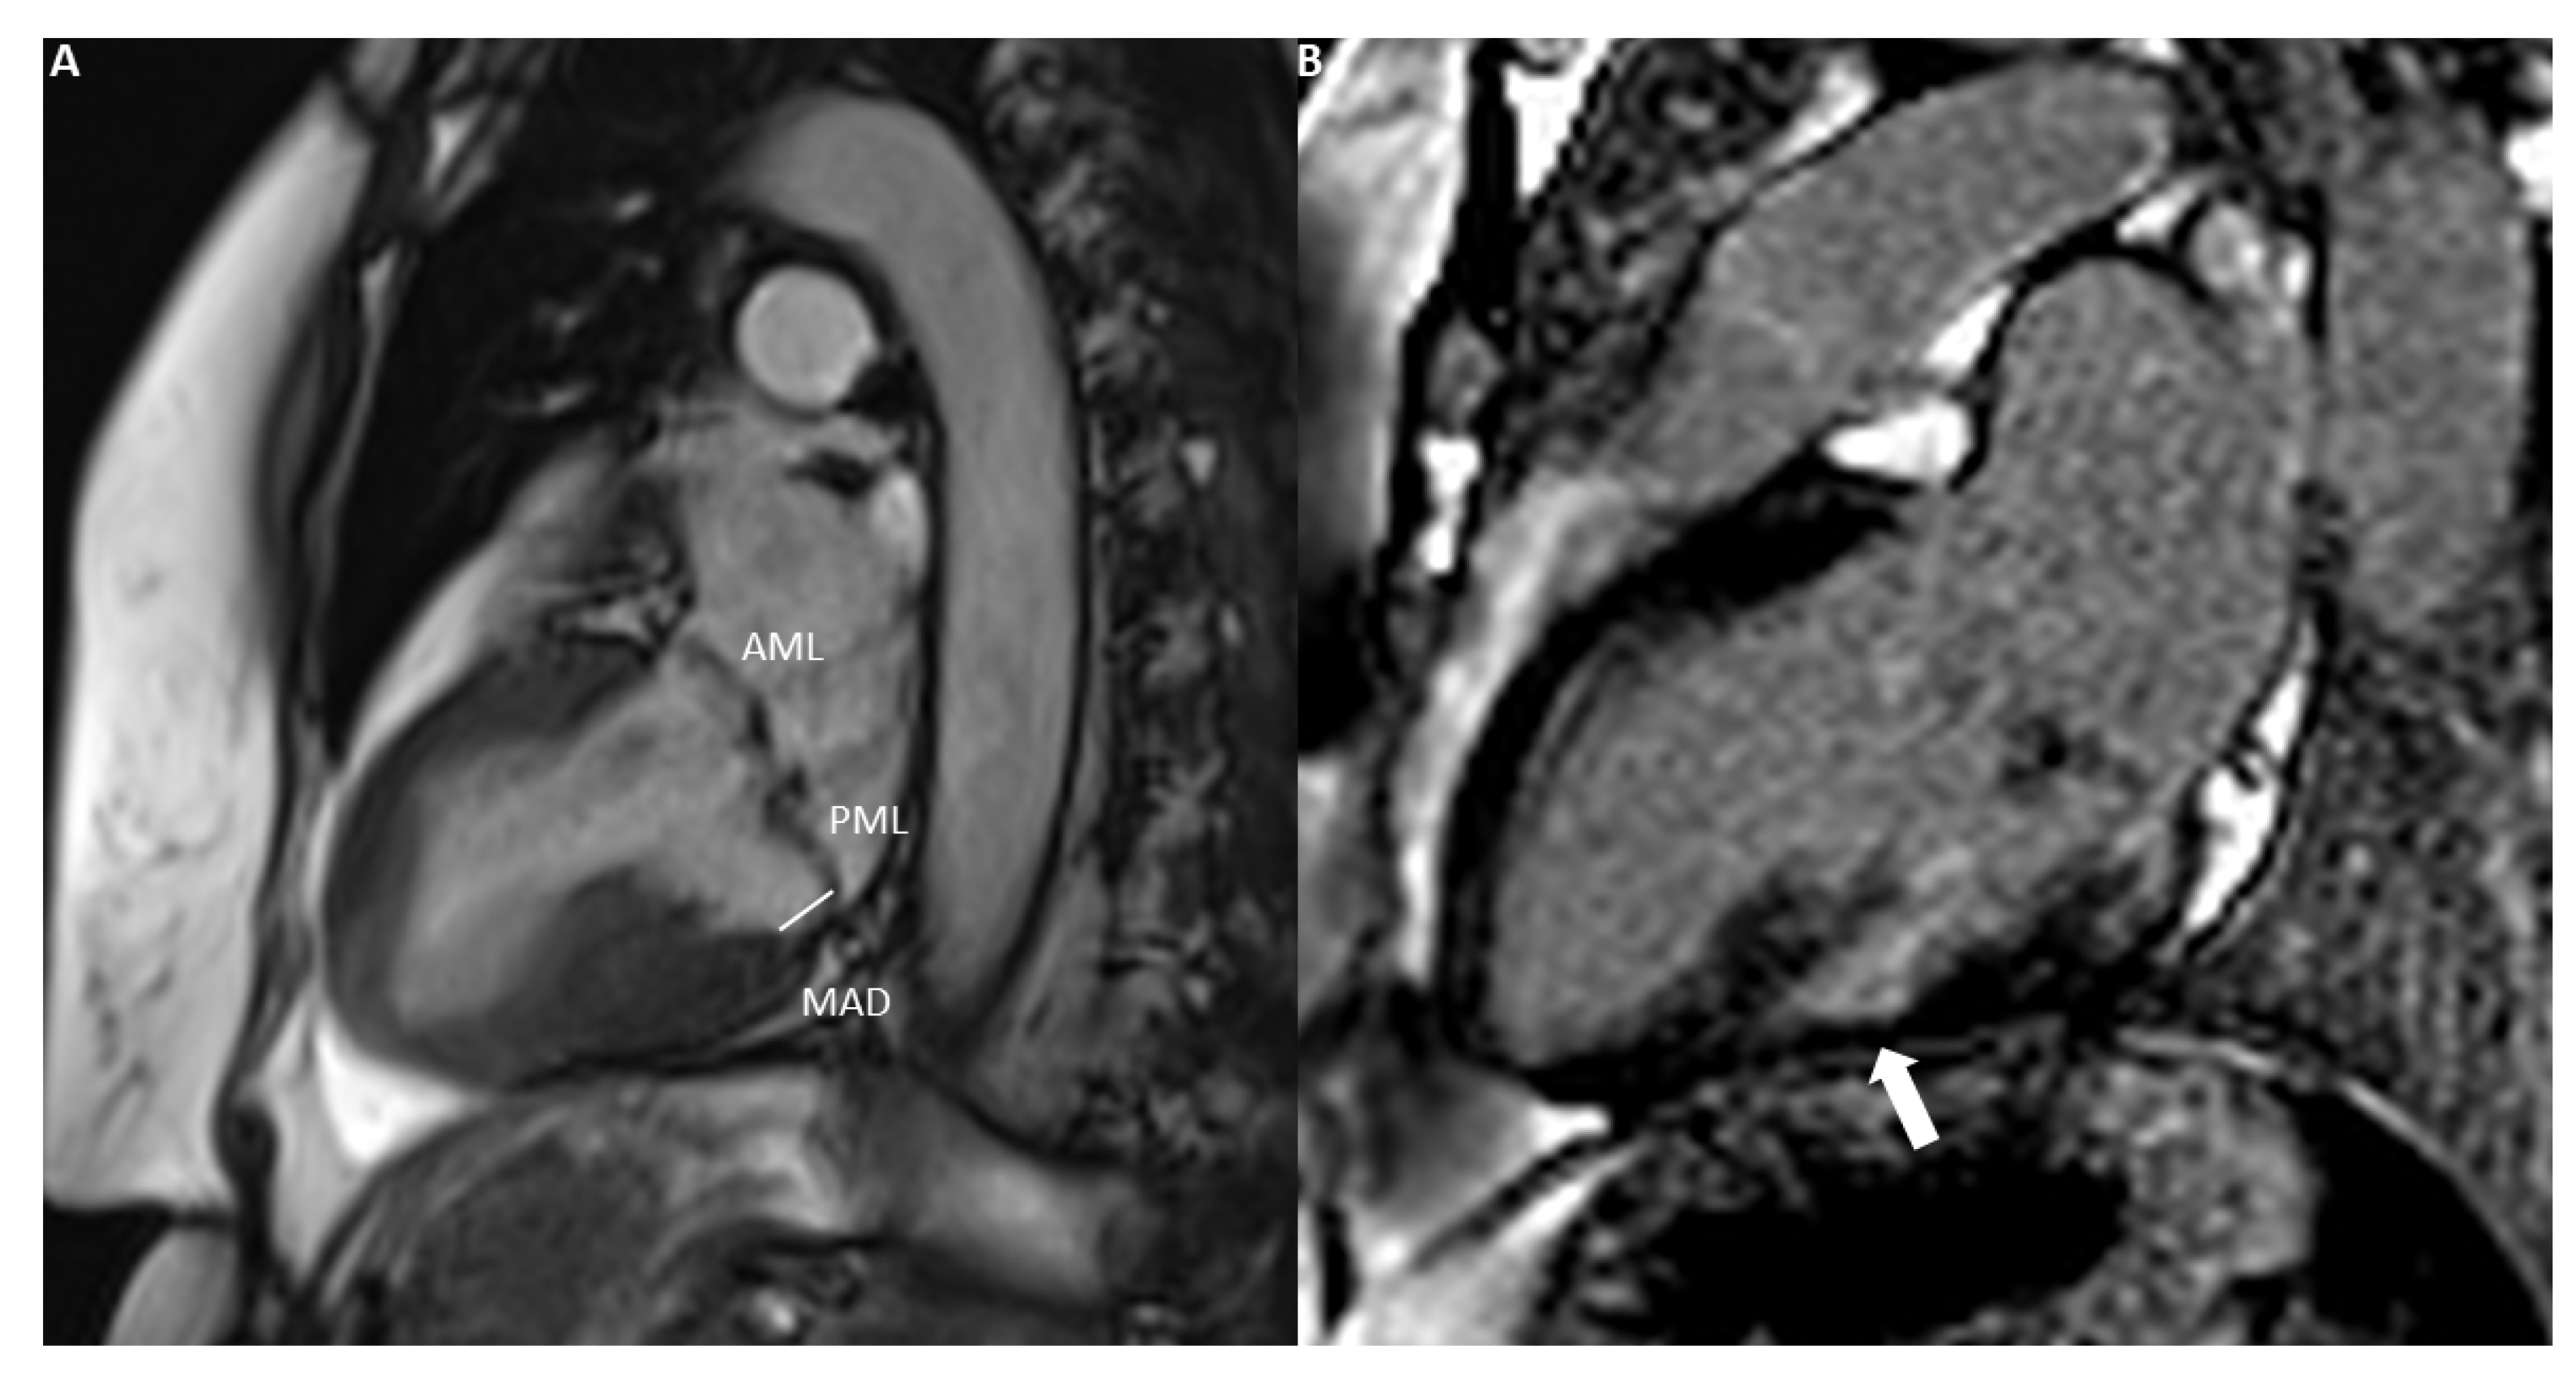

2. How to Assess Mitral Regurgitation with CMR

4. Application of CMR in Primary and Secondary Mitral Regurgitation